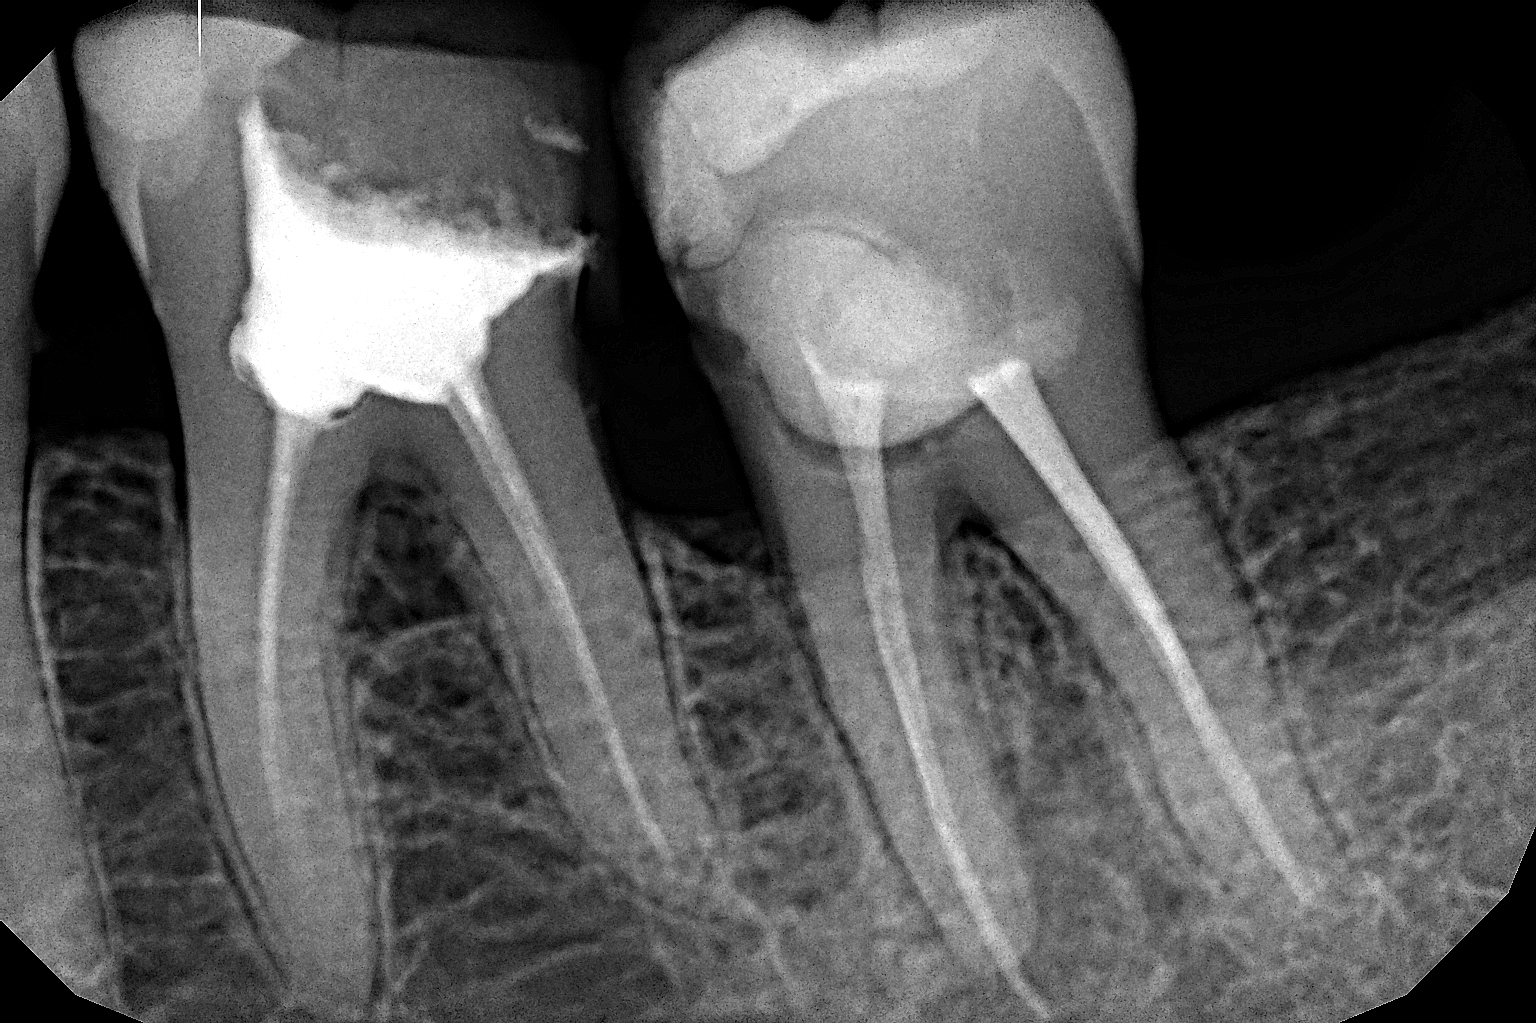

Особенности и порядок проведения рентгенографического обследования Порядка 60% тканей зуба находятся под десной, скрыты от визуального осмотра. Чтобы оценить их состояние, определить наличие проблемы и степень ее выраженности, назначить адекватное лечение, применяют рентгеновские лучи. Они беспрепятственно проникают через ткани вне зависимости от их плотности, формируя на пленке отпечатки:

- пломб, искусственных коронок и т. п., которые блокируют продвижение луча и отпечатываются в формате белых пятен;

- мягких тканей, дентина, эмали - они окрашены на снимке в серый цвет;

- воспалительных элементов - выглядят как темные пятна на пленке.

В ортодонтии рентген дает полную оценку качеству пломбирования корневых каналов зубов. В хирургии - чистоту удаления элементов зуба.

Прицельный снимок - простая, доступная и достаточно информативная процедура в стоматологической диагностической практике. Она позволяет посредством рентгенографического исследования получить картину о состоянии одной или 2-3 стоящих рядом единиц зубного ряда. Задачи, решаемые с помощью методики: - уточнение или постановка диагноза; - оценка интенсивности и динамики развития патологического процесса; - изучение качества запечатывания корневых каналов, восстановления костной ткани; - подбор оптимального курса терапии, контроль над ее ходом; - выявление скрытых патологий (трещин, переломов и пр.); - анализ фактического состояния корневых каналов, дентина, сосудов и костной ткани. В современной стоматологической диагностической практике для получения прицельного снимка зубов чаще всего используется цифровой радиовизиограф, дающий минимальную облучающую дозировку и позволяющий получить максимально полную и точную картину. Отсутствие рассеивания лучевого потока в момент проведения процедуры - дополнительный фактор в пользу ее безопасности для пациента. Показания к проведению Стоматолог назначает прицельный снимок в следующих случаях: - наличие болезненности в области зуба/зубов; - оценка степени повреждения зуба при получении травмы; - в качестве дополнительного или основного метода диагностики при кариесе, пульпите, периостите, периодонтите, кисте корневой; - оценка состояния, роста "зубов мудрости" - третьих моляров; - диагностика заболеваний десен - пародонтита, пародонтоза; - анализ деструкции, атрофии, дефицита костной ткани, степени выраженности и развития проблемы; - оценка качества проведения чистки корневых каналов зубов. В обязательном порядке процедура назначается перед хирургическими манипуляциями, коррекцией прикуса, протезированием. Виды процедуры Зависят от оборудования, с помощью которых проводится диагностика. Различают: - пленочные, дающие плоскостное изображение, качество которого теряется с течением времени уже в ближайшие 1-2 года после проведения; - цифровые, позволяющие расширить картину снимка в несколько раз, получить детальное изображение исследуемой области в высоком качестве разрешения. Цифровой снимок, в свою очередь, бывает двух типов: 1. Интраоральный - внутренний, для оценки кариеса прилегающих зубов, его лечения, степени прилегания пломб. 2. Интерпроксимальный - для анализа состояния коронковых частей. Используется для контроля над ходом и результатом протезирования, оценки пломбирования эндоматериалом кариозных полостей. Преимущества и ограничения в использовании методики К плюсам диагностической процедуры прицельного снимка относят: - его безопасность. Доза рентгеновского облучения минимальная. Абсолютно безопасно для здоровья допустимо сделать порядка 100 прицельных снимков в год и 6 - за одно посещение врача. Излучение минимальное, не затрагивает внутренние и рядом расположенные органы, не распространяется на соседние ткани; - четкость, высокое качество и разрешение полученного снимка; - удобное хранение серии последовательно сформированных снимков, оценка результата в динамике; - оперативность проведения; - возможность увеличения, приближения изображения, его детализации, распечатки по мере необходимости. Прицельный снимок - это высокоточная методики, позволяющая выявить стоматологические проблемы, скрытые патологии на самой ранней стадии их появления, еще до проявления характерных клинических признаков. Ограничения в возможностях методики - малая зона охвата, небольшой обзорный участок (максимум - 4 зуба), нельзя определить трещины в корнях, перфорацию. Ограничения по назначению Процедура не рекомендуется: - пациентам с низким иммунитетом; - после перенесенных заболеваний, травм; - при наличии кровотечений, внешних и внутренних; - в детском (до двух лет) возрасте. Беременность не является абсолютным противопоказанием к назначению прицельного снимка. Специалисты рекомендуют его проводить не ранее начала второго триместра беременности.